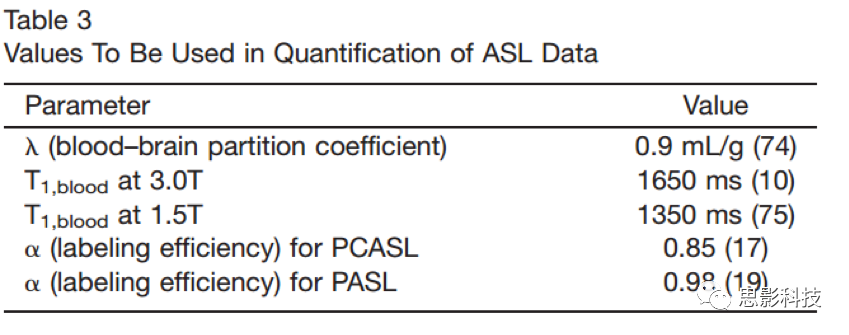

本文的目的在于为已有ASL灌注成像的临床应用提供补充意见,以提高数据的采集质量。ASL技术的发展至今已经20余年。ASL技术采集得到灌注影像质量已达到可用于临床以及研究应用的程度。但是经过多年的发展,有大量的标记方案以及各种模型实现脑血流(cerebral blood flow, CBF)的重建,这使得临床医生以及研究人员难以在各种方案中选择下最优的重建模型。使得构建各个部位的统计以及有意义的临床实验的建立变得复杂,这种广泛而无规范的实验操作减慢了在设备上应用ASL技术的速度,从而限制了该技术的推广。图1即为推荐参数下ASL扫描图像。

Figure 1 正常被试在推荐参数下asl扫描的图像

按照以上假设,可按照以下公式计算各个体素CBF,对于PCASL可用:

PASL可用:

其中l是脑血之比以mL/g为单位;而SIcontrol以及SIlabel是在控制与标记图像在标注时间内像素的平均值。T1Blood是以秒为单位的血液的弛豫时间,α是标注效率,SIpd是信号的加权灰度值,而t是标注时间。PLD,TI以及TI1的相关介绍如上文所述,该参数乘以6000可将单位有mL/g转化为mL/(100g)/min。针对2D多层采集图像来说,TI的区值需要将每个扫描层之间的获取间隔纳入考量,并作适应性调整。表三中罗列了在ASL扫描中推荐的一些常用参数可作参考。

为了将ASL图像的信号差值强度缩放到绝对CBF单位,需要测量完全放松下的血液自旋的信号强度。尽管有几种方法可以得出该值的估计值,但本文建议使用单独采集密度(PD)图像(在上述等式中由SIPD表示),以逐个像素的方式获得此比例因子。因子lambd测量组织与血液的信号强度。原则上,lambd应该是一幅图像,因为不同组织类型的组织水分密度不同,但通常使用大脑的平均值。测量l的策略以及不用l量化CBF的方法都已经提出了但还未广泛应用。与常数lambd假设相关的量化误差预计<10%。在这里,建议在进行更好的优化和替代策略的临床评估之前,至少要使用脑平均值lambd值。将PD图像用于此缩放具有两个附加的重要功能。

可视化

ASL技术的一个关键优势在于可得到绝对脑血流。本文建议采集人员以灰度或彩色查看生成的CBF图像,并在图像旁边使用定量比例尺指示CBF值(图8)。使用颜色可以提高从颜色棒读取定量CBF值的能力,但也可能导致错误的表观阈值,因此用户应注意这一潜在的陷阱。